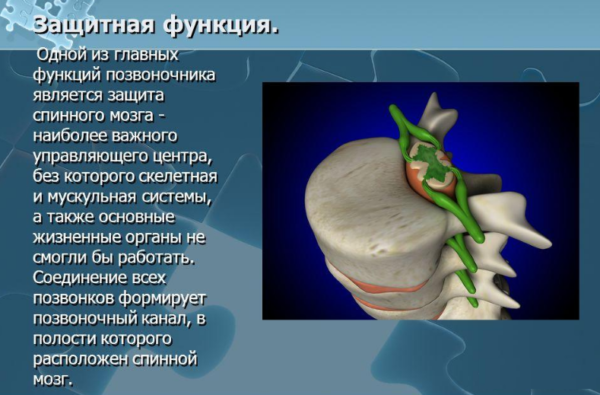

- Третья функция – защита. Под костной позвоночной оболочкой скрывается мозг, без исправной деятельности которого невозможно функционирование практически всех систем организма.

Защитная функция